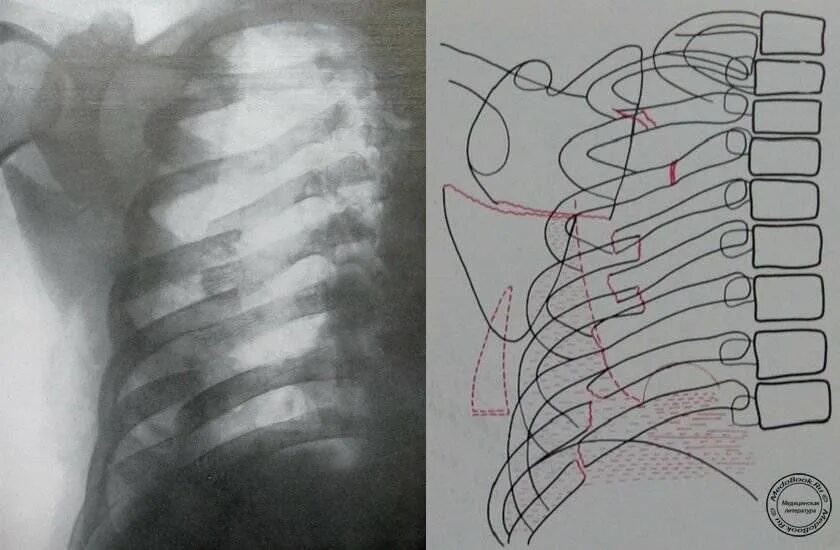

Как определить перелом ребра или ушиб